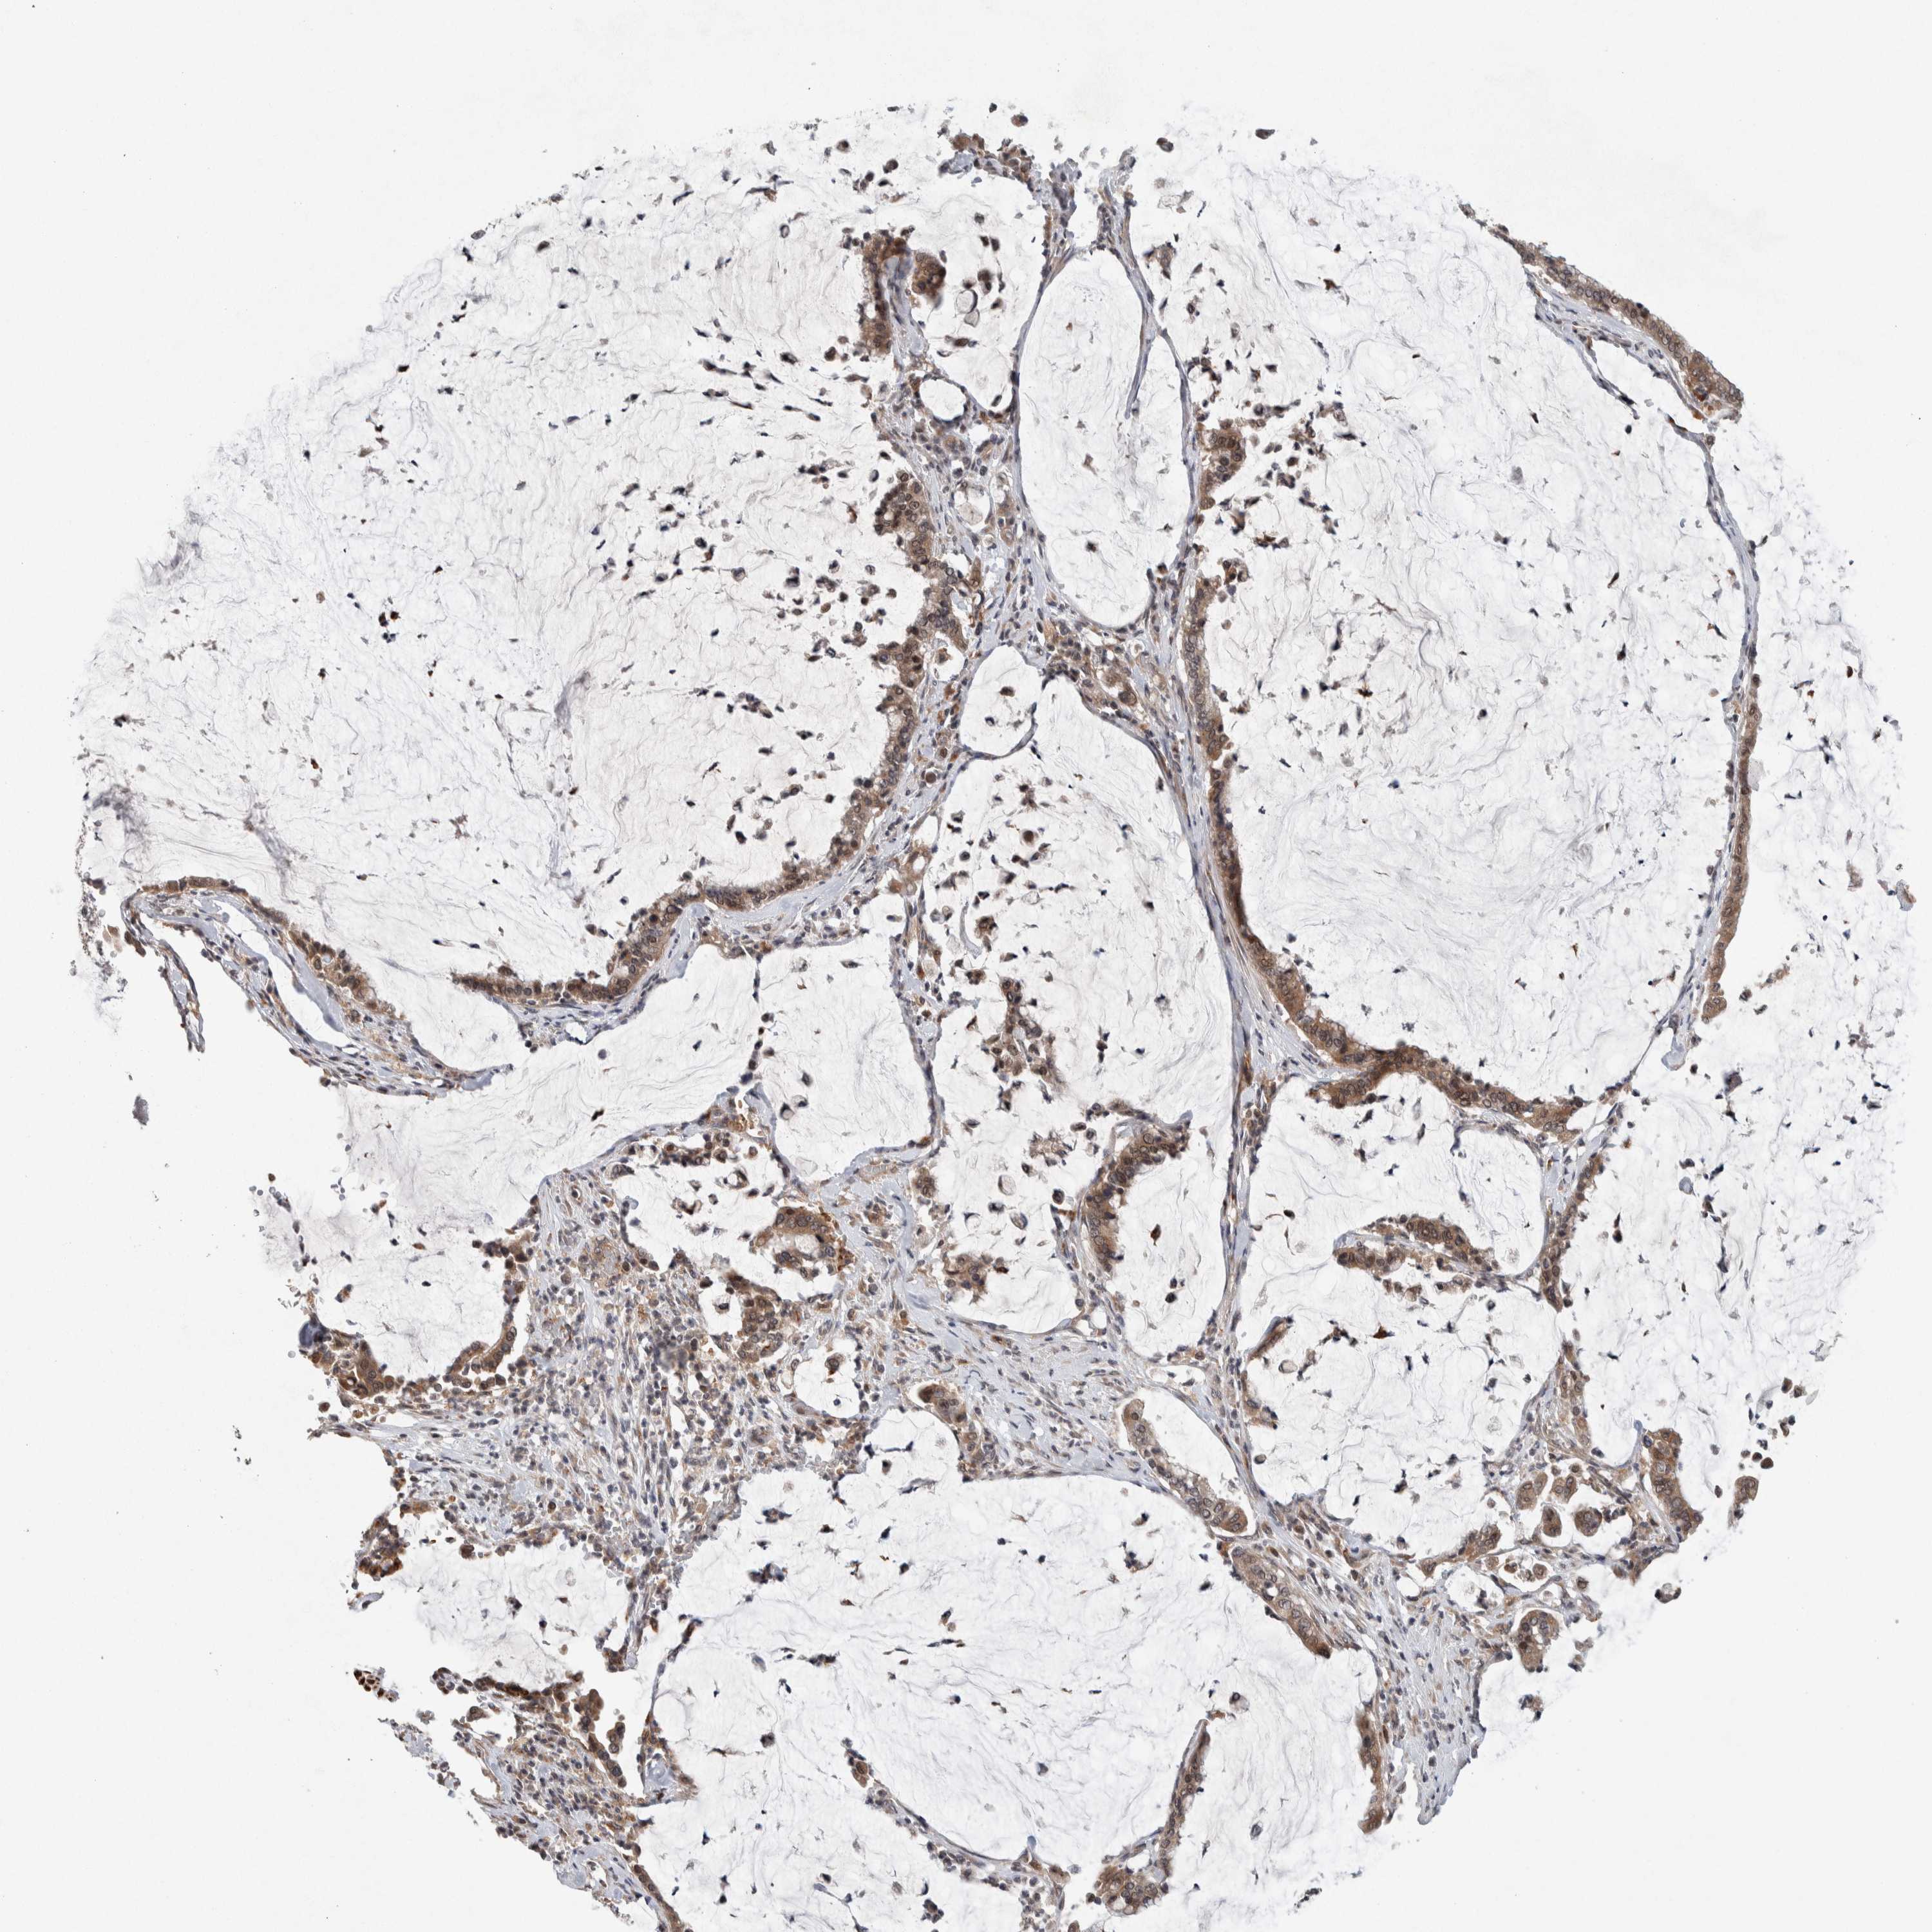

PANCREATIC CANCER - Protein expressioni

A mouse-over function shows sample information and annotation data. Click on an image to view it in a full screen mode. Samples can be filtered based on level of antibody staining by selecting one or several of the following categories: high, medium, low and not detected. The assay and annotation is described here.

Note that samples used for immunohistochemistry by the Human Protein Atlas do not correspond to samples in the TCGA dataset.

Antibody stainingi

Antibody staining in the annotated cell types in the current human tissue is reported as not detected, low, medium, or high, based on conventional immunohistochemistry profiling in selected tissues. This score is based on the combination of the staining intensity and fraction of stained cells.

Each image is clickable and will lead to virtual microscopy that enables deeper exploration of all samples and also displays staining intensity scores, fraction scores and subcellular localization as well as patient and tissue information for each sample.

Antibody HPA016049

Antibody CAB022588

Staining

High

Medium

Low

Not detected

Intensity

Strong

Moderate

Weak

Negative

Quantity

>75%

75%-25%

<25%

None

Location

Nuclear

Cytoplasmic/membranous

Cytoplasmic/membranous,nuclear

Adenocarcinoma, NOS

Adenocarcinoma, metastatic, NOS